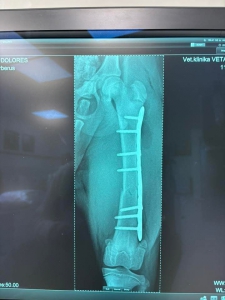

Včera sme prijali toto zranené šteniatko. Fenka zostala na pozorovanie na veterine a zistili že má zlomenú stehennú kosť :(

TERMÍN OPERÁCIE JE ZAJTRA 12:00 U PÁNA DOKTORA ADAMAŤA V TRENČÍNE

DOLORES má po operácii ♥. Ďakujeme všetkým za pomoc ♥♥♥. Držte malej palce aby bola čoskoro fit :)

Dolores po operácii pozdravuje. Zotavuje sa výborne a rýchlejšie ako sme mysleli ♥♥♥